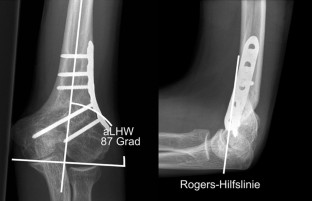

Die Pseudarthrose des kindlichen Condylus radialis humeri mit posttraumatischem Cubitus valgus stellt nach inadäquater Behandlung eine ernsthafte Komplikation dar. Wir berichten über einen damals 14-jährigen männlichen Patienten, der nach konservativer Frakturbehandlung des Condylus radialis humeri eine zunehmende Fehlstellung im Sinne eines Cubitus valgus entwickelte. Nach Durchführung einer Schraubenosteosynthese wurde nach gesicherter Konsolidierung eine erfolgreiche suprakondyläre Domosteotomie vorgenommen, die zur Beschwerdefreiheit und freien Beweglichkeit des Ellenbogengelenks führte.

Non-union of the pediatric lateral humeral condyle following post-traumatic cubitus valgus is a severe complication after inadequate treatment. We report on a then 14-year-old male patient who developed an increasingly defective position in terms of cubitus valgus after conservative treatment of a lateral humeral condyle fracture. After performing screw osteosynthesis and achieving consolidation, a successful supracondylar dome osteotomy was performed which led to relief from pain and free range of motion of the elbow joint.

Abb. 4